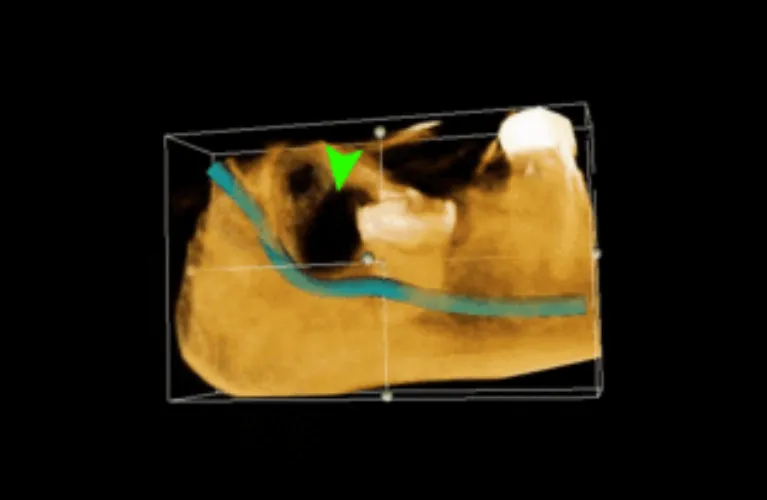

Pre-Operative Xray Required

OPG

CBCT